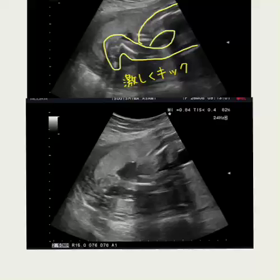

予定日まであと98日

2017年6月16日